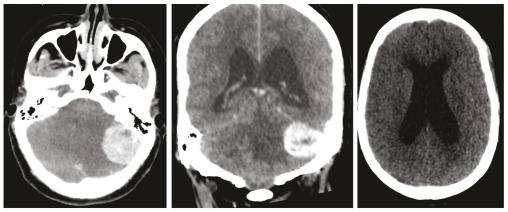

Une femme de 32 ans, sans antécédents pathologiques, consulte pour baisse brutale de l’acuité visuelle. L’examen ophtalmologique trouve un œdème papillaire bilatéral, le reste de l’examen neurologique est sans particularités. Face à cette symptomatologie, un scanner cérébral est réalisé en urgence. Il montre un processus cérébelleux gauche responsable d’un effet de masse sur le quatrième ventricule avec une hydrocéphalie d’amont et des signes de résorption transépendymaire (fig. 1 ). Par la suite, la patiente a bénéficié d’une dérivation ventriculo-péritonéale. Une imagerie par résonance magnétique (IRM) cérébrale a été réalisée pour une meilleure analyse. Elle a permis d’objectiver un processus intra-axial cérébelleux gauche bien limité à double composante kystique et charnue majoritaire en hyposignal T1-hypersignal T2 sans restriction sur la diffusion et se rehaussant de façon intense après injection de chélates de gadolinium (fig. 2 ). La patiente a été opérée (résection en monobloc de la tumeur) (fig. 3 ). Le diagnostic d’hémangioblastome a été confirmé à l’examen anatomopathologique. La patiente s’est améliorée par la suite sur le plan neurologique mais elle a conservé une cécité définitive.